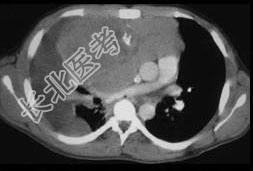

- 单项选择题女,34岁, 咳嗽,咯血半月余, 请结合影像学检查,选出最可能的诊断 ( )

A、纵隔畸胎瘤

B、淋巴瘤

C、胸腺瘤

D、神经源性肿瘤

E、肺癌